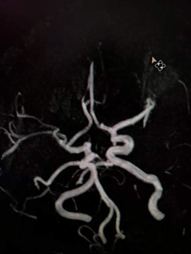

When studying 120 MR-angiograms of individuals without disorders of cerebral circulation we have found the typical anatomy of Willis circle in 32% of cases only (Figure 1). In other 68% of patients from this group, the different variations were found, namely: hypoplasia/aplasia of the anterior communicating artery was noted in 23% (Figure 2), aplasia or hypoplasia of one of the posterior communicating artery in 21% of cases, 17% of patients showed the combination of both anterior and one of the posterior communicating arteries, aplasia of the anterior and both posterior communicating arteries were noted in 4% of cases, the parietal contact of both anterior cerebral arteries were found in 3%.

Figure 2 Hypoplasia/aplasia of the anterior communicating artery.